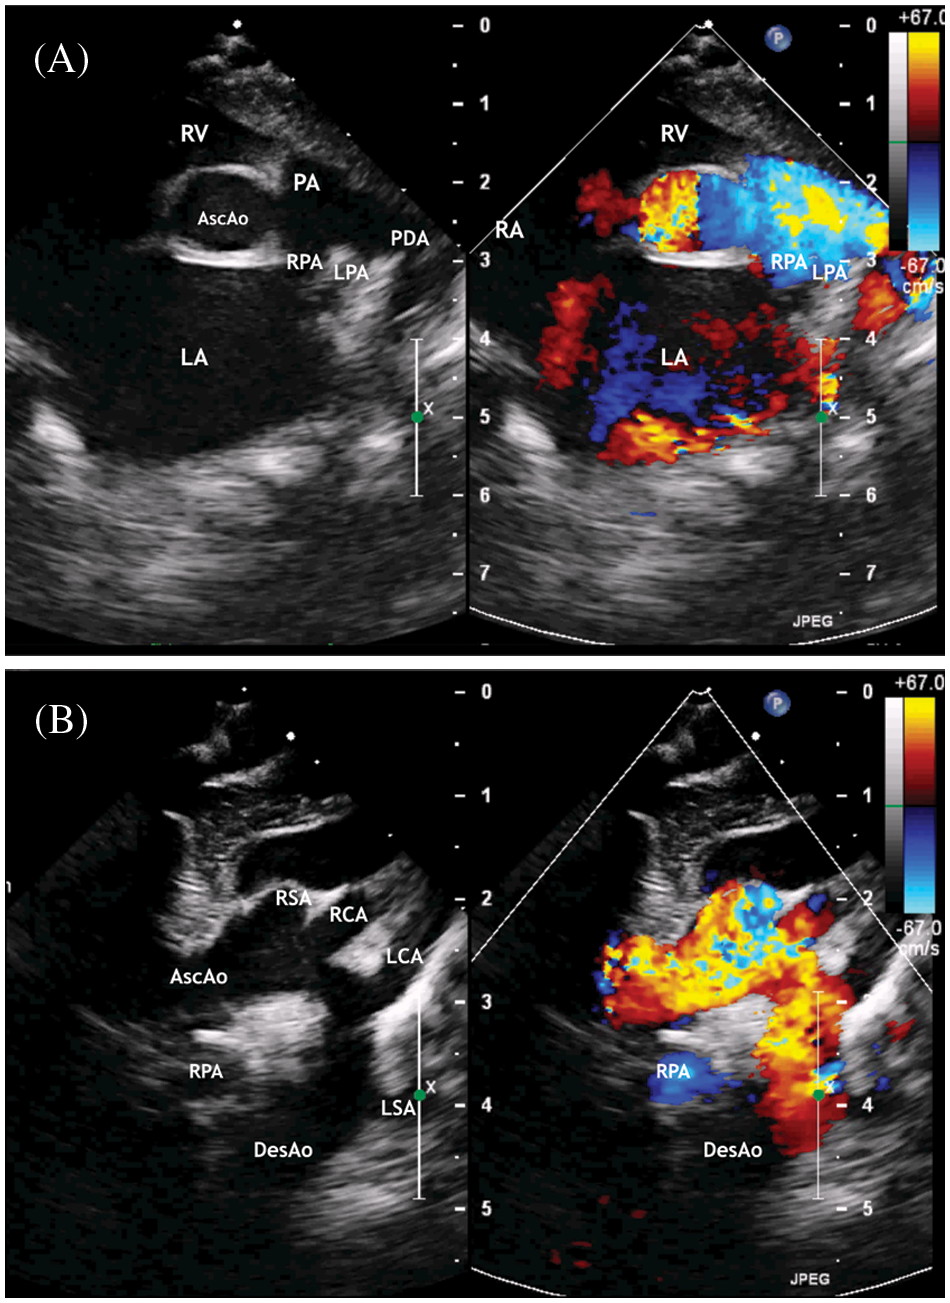

Figure 3: ECHO. (A) Parasternal short axis view. Enlargement of the left atrium. The patent ductus arteriosus with right to left shunt. (B) Suprasternal view. The ascending aorta is determined, mild aortic arch hypoplasia, and brachiocephalic vessels

Abbreviation: AscAo, the ascending aorta; DesAo, the descending aorta; LCA, RCA, the left and right common carotid artery; LSA, RSA, the left and right subclavian artery; RV, the right ventricle; RA, the right atrium; PA, the pulmonary artery; LPA, the left pulmonary artery; RPA, the right pulmonary artery; AscAo, the ascending aorta.